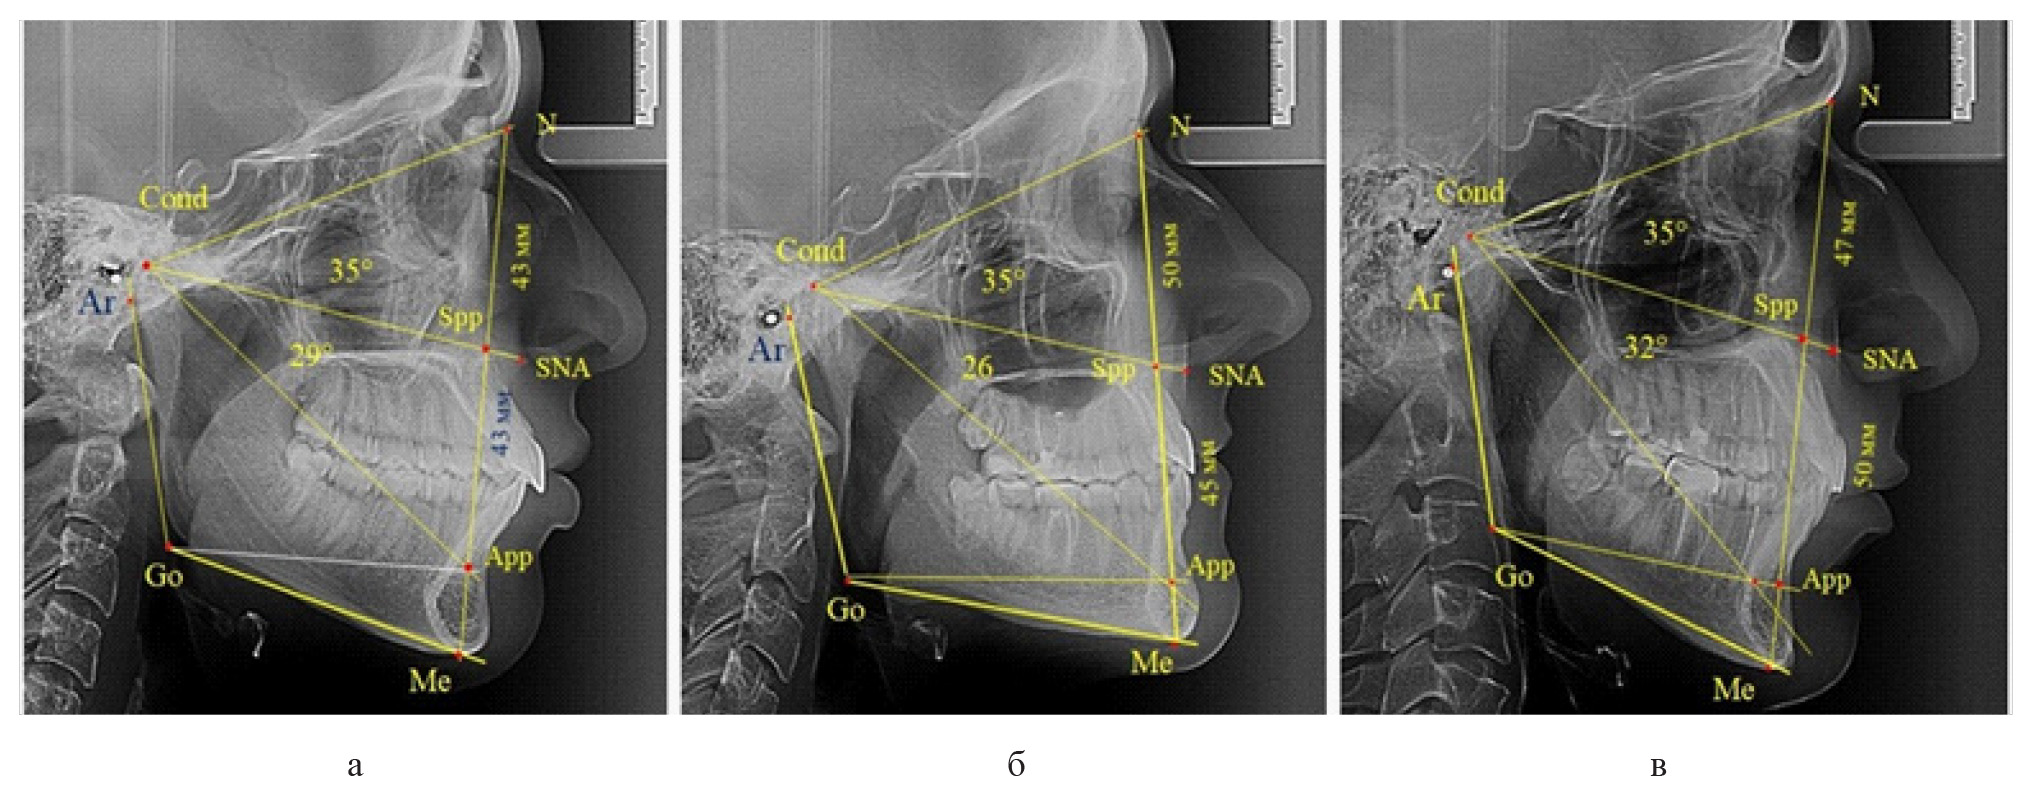

Вертикальная линия передней высоты лица (N-Me), после ее пересечения с линией Cond-SNA, определяла положение точки Spp, при этом вертикаль N-Spp использовалась в качестве оценки высоты назального отдела лица. Продолжение линии Go-Api до пересечения с линией N-Me позволяла определить положение конструктивной точки Арр и оценить линейные размеры гнатической части лица по величине вертикали Spp-Арр (рис. 1).

Рис. 1. Методы оценки основных параметров ТРГ для определения вертикальных размеров лицевого отдела головы

Величина угла назального отдела лица (N-Cond-SNA) в исследуемой группе составила (35,28 ± 0,26)°, а линейные размеры (N-Spp) были (48,82 ± 0,96) мм. Параметры угла гнатической части (SNA-Cond-App) были (29,83 ± 0,54)°, при линейной высоте (49,25 ± 1,31) мм.

Рис. 3. Сравнительный анализ ТРГ с оптимальными размерами носового отдела и оптимальными (а), укороченными физиологическими (б) и увеличенными физиологическими (в) размерами гнатической части лица